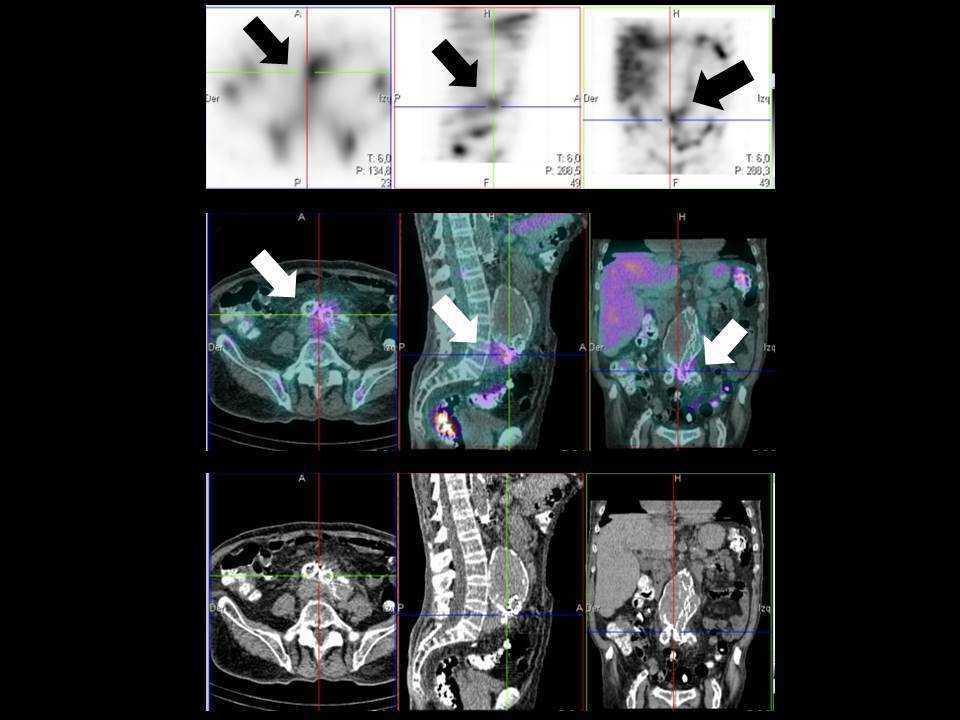

El paciente acudió a Urgencias, procediéndose a su ingreso, por fiebre de 39 °C y dolor abdominal continuo localizado en región periumbilical e hipogastrio. El control analítico mostró urea 94 mg/dl, creatinina 7,73 mg/dl, proteína C reactiva 29,60 mg/dl, procalcitonina 0,895 ng/ml; hemograma: hemoglobina 10,8 g/dl, leucocitos 14 300/uL (neutrófilos 86 %, linfocitos 18 %) y plaquetas 181 000/uL. La tomografía computarizada de emisión monofotónica (SPECT/TAC) de abdomen con Ga67-citrato (figura 1) puso de manifiesto la presencia de un proceso infeccioso localizado en la endoprótesis aorto-ilíaca2. En los hemocultivos se aisló Listeria monocytogenes. Se inició tratamiento con ampicilina, amikacina y vancomicina durante seis semanas3. El paciente mejoró, con desaparición de la fiebre y del dolor abdominal, normalización de los parámetros inflamatorios y negativización de los hemocultivos. Se repitió la SPECT/TAC de abdomen con Ga67-citrato a las tres semanas, con desaparición del depósito patológico abdominal.

Figura 1.